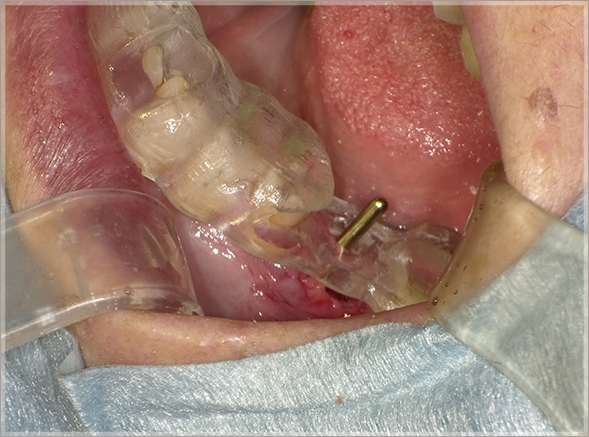

2.抜歯窩にPRGFの処置をします

③PRGF(F2+骨補填材Bio-Oss)填入

④抜歯窩を十分に満たす

3.メンブレンで抜歯窩を閉鎖します

⑤F1メンブレン作製

⑥F1にて抜歯窩を閉鎖する